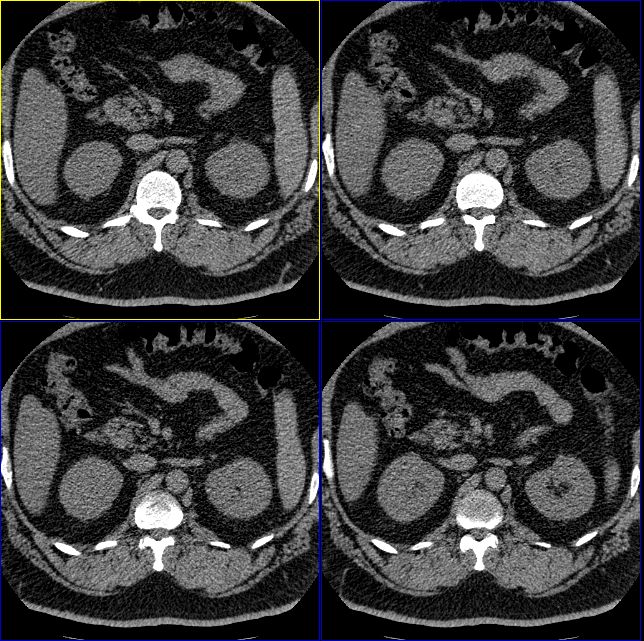

男性,37岁。体型极度肥胖,达300余斤。

支持脂肪肝,从图象看脾的密度要高于肝的

肝脏密度普遍减低,从图象看低于脾脏,支持脂肪肝。

脾v扩张、迂曲 脂肪肝,早期肝硬化

标题: 双侧肾上腺没有问题么?

怎么回事啊,难道肾上腺没有问题么?右侧肾上腺有明显的脂肪性类圆形肿物,左侧也觉得有增生性改变。我们诊断为右肾上腺髓样脂肪瘤,左侧肾上腺增生。大家再仔细看看。

肝脏密度普遍减低,从图象看低于脾脏,支持脂肪肝。必要时增强扫描

脂肪肝是有的,楼主说的右侧肾上腺囊性灶是不是衬出的假象,密度如何,建议测测